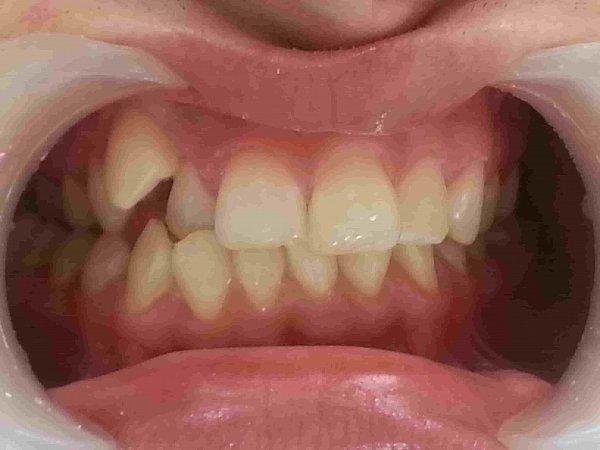

Пациентка 13 лет. Обратилась с жалобой на неправильный прикус.

Объективно: обратная резцовая окклюзия, вестибулярное положение зуба 2.3(клык) отсутствие зуба 1.2 (первичная адентия), сужение верхней челюсти, перекрёстная окклюзия справа, из анамнеза ротовое дыхание и аденоиды.

План лечение:

1)Расширение верхней челюсти с помощью аппарата РПЕ;

2)Удаление зубов мудрости нижней челюсти;

3)Лечение на брекет системе 2 челюсти с использованием техники многопетлевой дуги и ношениеэластических тяг.

4)Имплантация в области бокового резца после 18 лет

5)Лечение у ЛОРа.

Достигнуты результаты за 11 мсяцев:

1)расширение верхней челюсти

2)устранение обратного резцового перекрытия;

3)устранение скученности верхней челюсти;